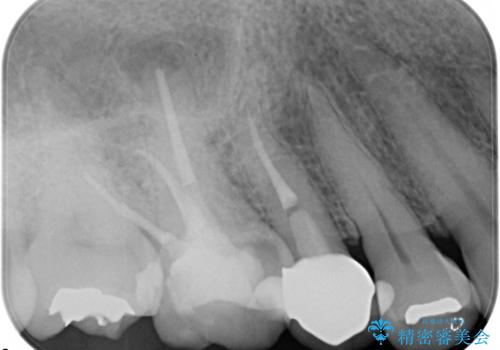

- 定期検診にて、奥歯の頬側歯肉にサイナストラクトが発見された患者様です。

根管治療から歯冠修復まで行っております。

サイナストラクト(瘻孔)から原因歯を特定し治療を行っております。根管治療を行った歯牙は破折リスクが高くなるため被せものによる治療を提案しております。